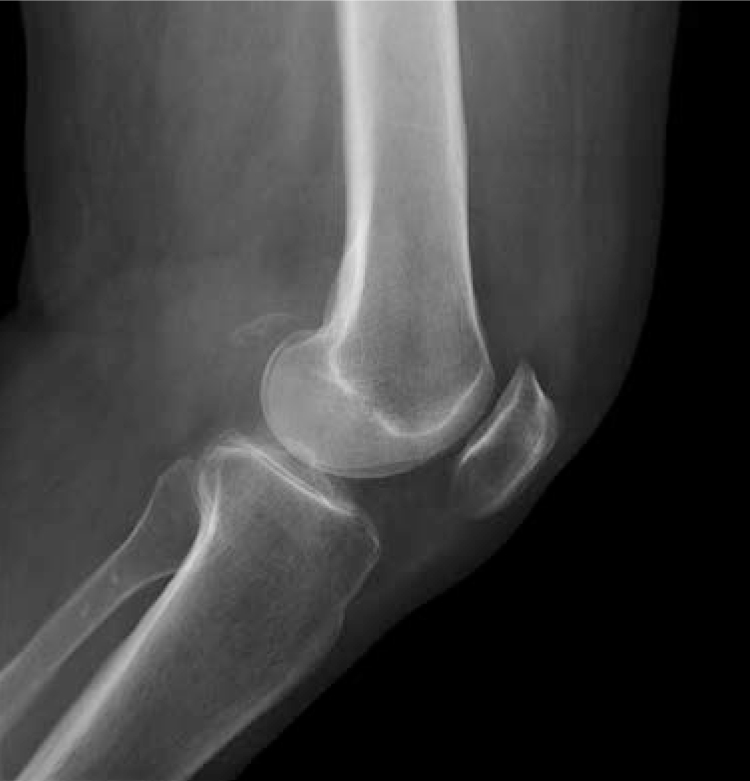

A 69-year-old woman presented to her primary care physician with pain and decreased range of motion in her left knee for the past 5 days. She reported no history of trauma. The patient underwent an arthrocentesis and received a 1.5-mL injection of triamcinolone, which improved her pain and range of motion. She returned 9 months later with the same symptoms lasting for 3 days. Physical examination revealed decreased flexion and extension and fullness in the posterior joint space. Laboratory studies revealed a high erythrocyte sedimentation rate (63 mm/h) and C-reactive protein level (7.66 mg/dL). Plain film radiograph of the knee showed calcification in the popliteal fossa (image). Calcium pyrophosphate crystals were identified in the synovial fluid, and calcium pyrophosphate deposition disease was diagnosed. She was given a 1.2-mg dose of colchicine orally, followed by a 0.6-mg dose 6 hours later, which resolved her symptoms and improved her range of motion.